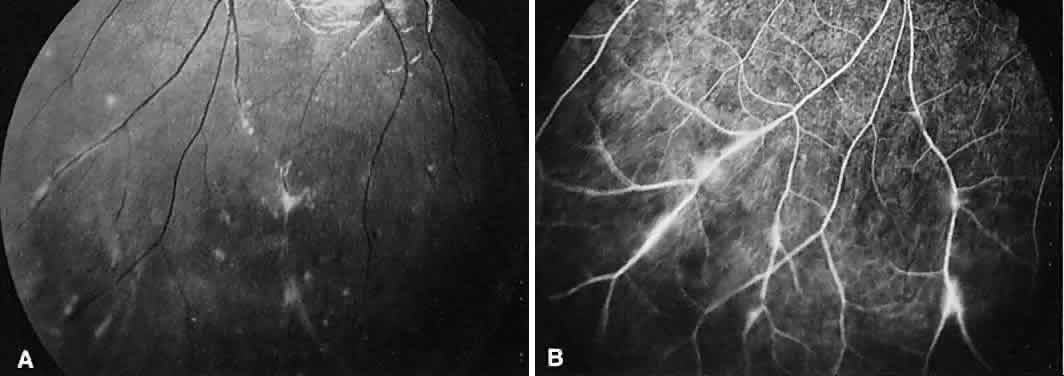

INTERMEDIATE UVEITIS

Intermediate uveitis is also known as pars planitis, peripheral uveitis, and chronic cyclitis. Intermediate uveitis is an inflammatory disease that affects young adults, causing symptoms of photophobia, floaters, and blurry vision. Clinically, mild anterior chamber inflammation, vitreous cells, vitreous snowballs, inflammatory membranes on the pars plana, phlebitis, cystoid macular edema, and, rarely, choroidal and retinal neovascularization are seen.

On fluorescein angiography, there is venular wall staining (Fig. 9),30 hyperfluorescence, and leakage of the peripheral inflammatory membranes.31 Cystoid macular edema often is evident.30 Optic disc, peripheral retinal, and subretinal32–34 neovascularization are rare.

Fig. 9. Intermediate uveitis. A. Red-free photography of the peripheral retina shows sheathing of the retinal venules. B. Fluorescein angiography shows staining of the vessel walls with leakage from the peripheral venules.